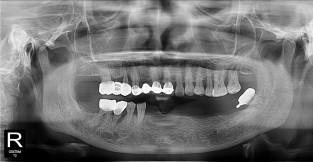

하악

치료기간 : 2021-11-30 ~ 2022-07-13

1. 상기 x-ray 이미지 모두 동일한 해당 의료기관에서 진료한 환자입니다.

2. 상기 x-ray 이미지 모두 동일 인물의 것입니다.

3. 치료 전 이미지는 2021-11-30에 촬영했으며, 치료 후 이미지는 2022-07-13에 촬영하였습니다.

4. 상기 x-ray 이미지 모두 동일 조건에서 환자분의 동의를 받아촬영되었습니다.

* 임플란트 시술은 환자분의 상태(고혈압, 당뇨 등)에 따라 부작용이 있을 수 있으니, 반드시 전문의와 상담이 필요합니다.

* 임플란트 수술 부작용

: 수술 후 출혈, 교합, 통증, 붓기, 염증 등의 문제점이 발생할 수 있습니다.)

* 본 이미지들은 의료광고법을 준수하여 게시하였으며, <의료법 제 56조 제2항 제7호>에 의거하여 개개인의 신체 상태와 질병 진행도 등 여러 요인에 따라 치료 효과가 상이하기에 진료계획 또한 달라질 수 있음을 고지해드립니다.